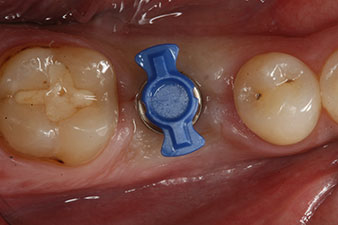

measuring probe

Fig. 6: Ten weeks later the gingiva former, which was screwed in place after placement of the implant, can be removed. In the linguo-buccal direction the ISQ value was virtually unchanged at 63 (measuring probe in proximity at a distance of 2-3 mm).

These values could have indicated open healing or even immediate restoration. Due to the insufficient crestal bone volume at the implant, the region was augmented with the bone chips collected during preparation of the implant bed and sutured to exclude saliva.

The implant was uncovered two months later and a gingiva former was screwed in (no picture).